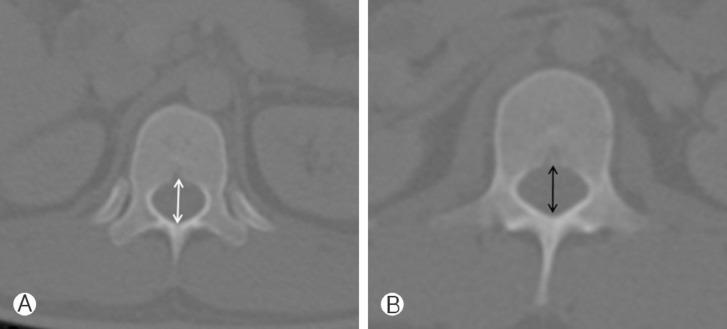

From PET/CT, axial bone-window CT of 83 young adults (20-29 years) were obtained, and we measured AP diameters of C3, C5, C7, T1, T4, T8, T12, L1, L3, L5 and S1. We also measured exposed AP diameter of C3, C5, C7, T1 and T2 above imaginary line for laminectomy.

The shortest mean AP diameter was at C5 (14.5±1.5 mm), and the longest was at S1 (17.4±2.3 mm). AP diameter increased from C3 (14.6±1.1 mm) to T1 (16.1±1.2 mm) at cervical spine. In the thoracic spine, the diameter gradually decreased from T1 (16.1±1.2 mm) to T8 (14.6±1.3 mm) and increased to T12 (16.7±1.2 mm). The diameter decreased from L1 (16.7±1.3 mm) to L3 (15.7±1.9 mm), and it increased to S1 (17.4±2.3 mm) at lumbar spine. Exposed AP diameter above imaginary line for laminectomy was the longest at C3 (4.8±1.2 mm) and gradually decreased to T1 (3.3±0.9 mm) and T2 (0 mm).

从PET/CT获取83名20 - 29岁年轻成年人的轴向骨窗CT图像,测量C3、C5、C7、T1、T4、T8、T12、L1、L3、L5和S1的前后径。我们还测量了椎板切除假想线上方C3、C5、C7、T1和T2的暴露前后径。

平均前后径最短处为C5(14.5±1.5mm),最长处为S1(17.4±2.3mm)。颈椎处前后径从C3(14.6±1.1mm)至T1(16.1±1.2mm)增大。胸椎处,直径从T1(16.1±1.2mm)逐渐减小至T8(14.6±1.3mm),然后增大至T12(16.7±1.2mm)。腰椎处直径从L1(16.7±1.